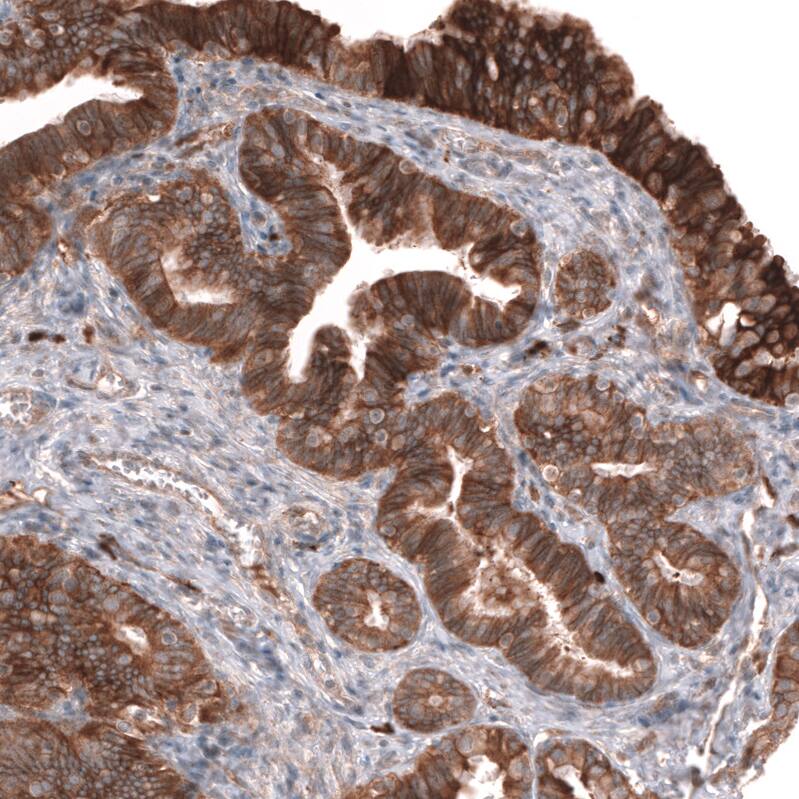

Immunohistochemistry-Paraffin: ADAM10 Antibody (CL13808) [NBP3-24577]

Analysis in human prostate and skeletal muscle tissues using NBP3-24577 antibody. Corresponding ADAM10 RNA-seq data are presented for the same tissues.